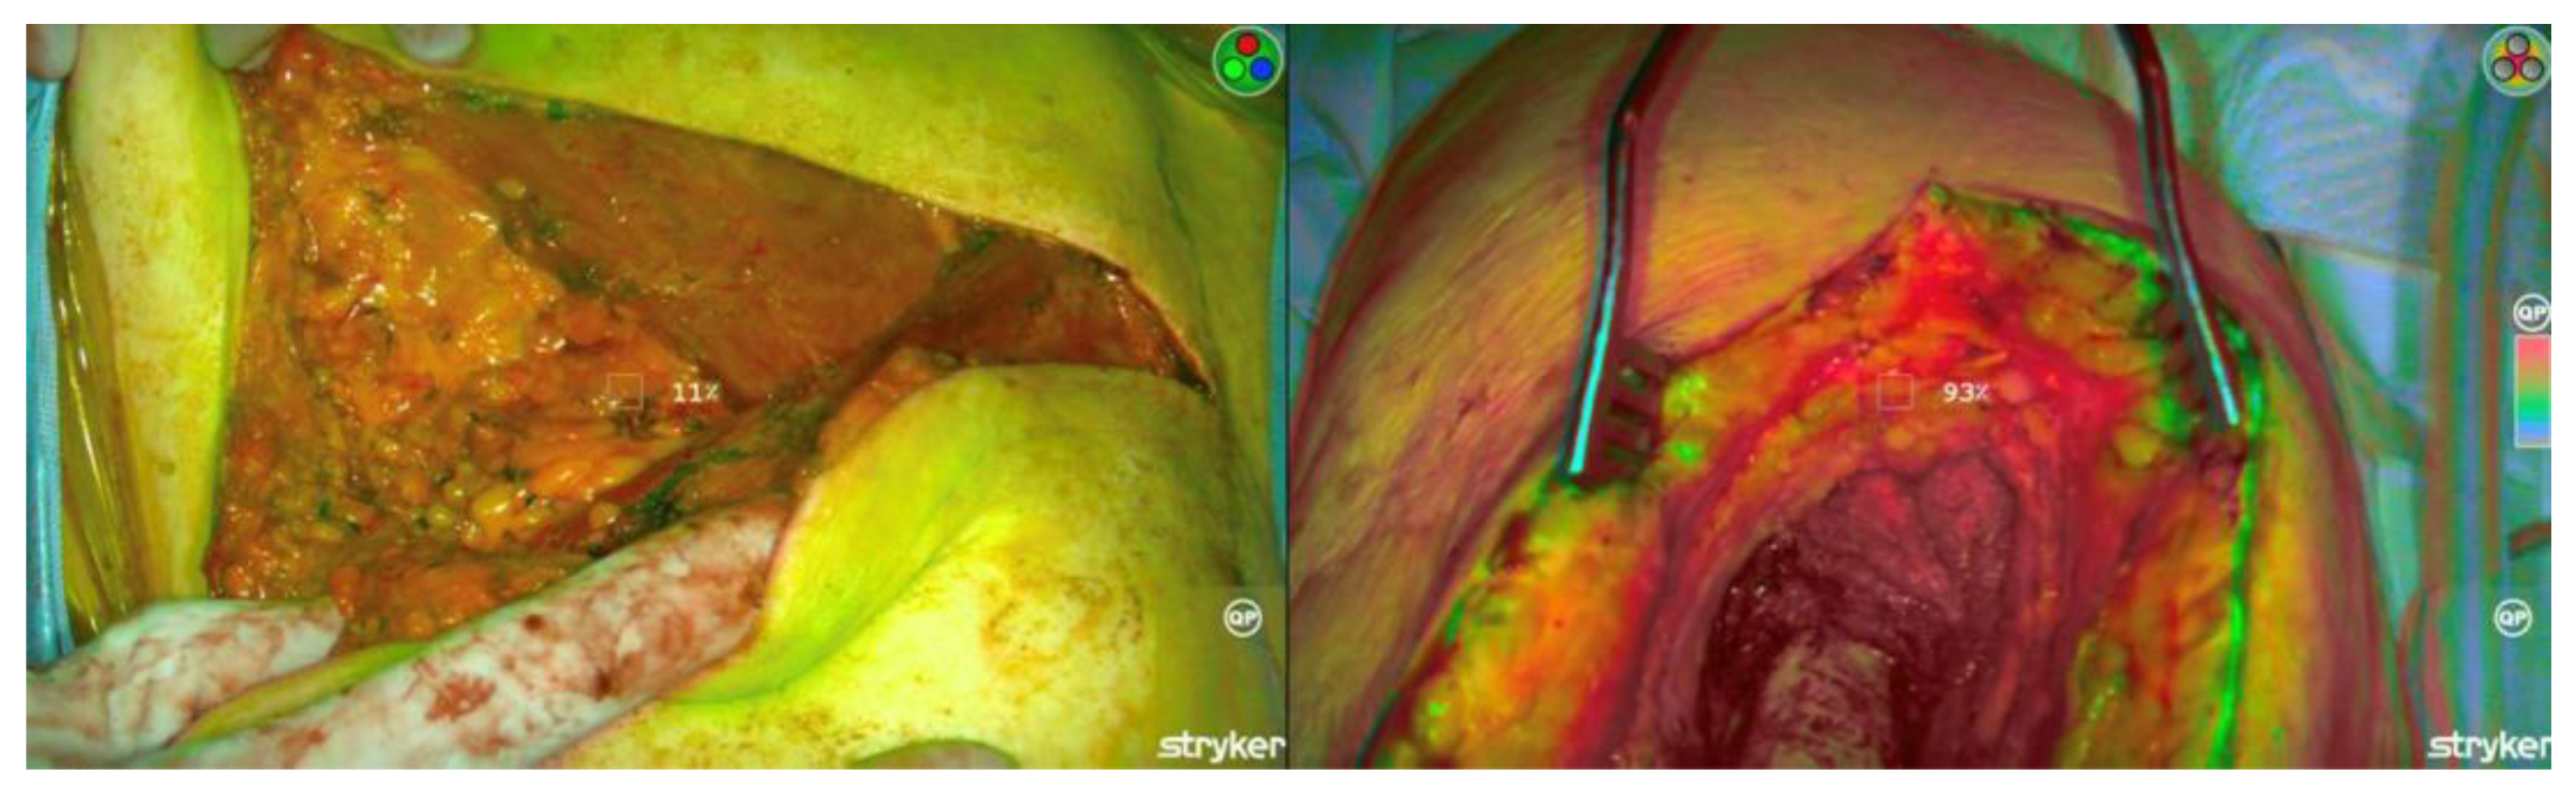

Intraoperative Evaluation of Soft Tissue Sarcoma Surgical Margins with Indocyanine Green Fluorescence Imaging

3.2. ICG Dosage, Duration, and Detection

3.3. ICG Margin Comparison